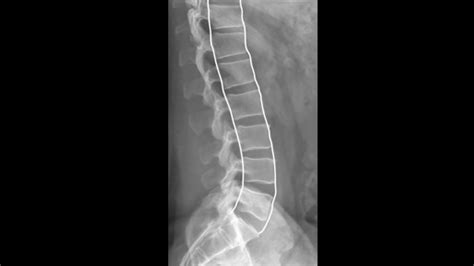

Assess the Overall Alignment: Begin by evaluating the overall alignment of the lumbar spine. Look for any signs of scoliosis, kyphosis, or lordosis. Abnormal curvatures can indicate underlying issues such as muscle imbalances, degenerative diseases, or congenital conditions. Utilize the

box to highlight standout information, such as the importance of assessing the lumbar lordosis, which is the inward curvature of the lower back.Evaluate Disc Space: The disc spaces between the vertebrae should be relatively uniform. Narrowing of the disc space can indicate degenerative disc disease, while widening may suggest ligamentous injury or infection. Use elements to compare the normal and abnormal disc spaces, providing a clear visual representation of the differences.

Look for Spondylolisthesis: Spondylolisthesis, the forward displacement of a vertebra, can be graded from 1 to 4 based on the percentage of slip. It’s essential to measure and record any slip to monitor progression or improvement. Create a

section to guide readers through the process of measuring and grading spondylolisthesis.Evaluate the Sacrum and Coccyx: Although not part of the lumbar spine, the sacrum and coccyx should be included in the assessment for any signs of fracture, dislocation, or degenerative changes that could affect the lumbar spine. Implement